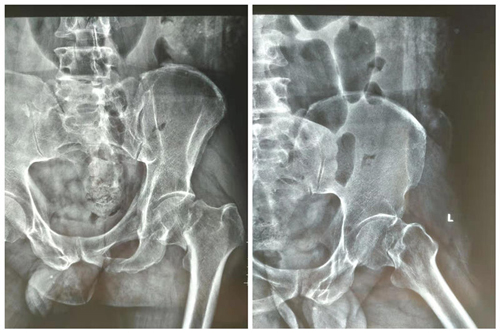

患者术前X线

8月15日,有一名52岁男性患者,癫痫发作摔倒致左髋部疼痛伴活动受限2天,诊断为股骨颈骨折(gardanⅣ型),既往有癫痫病史30余年,每月发作2次左右,最近几年发作频繁,依从性差,考虑拉力空心钉固定术后三个月内不能负重,3-6个月内部分负重,而且股骨头坏死率极高,针对这种具有高脱位风险患者,经过术前缜密计划,充分沟通,决定对患者行前路微创全髋关节置换术(DAA),微创骨科团队独立完成了此项手术,患者一周后康复出院。